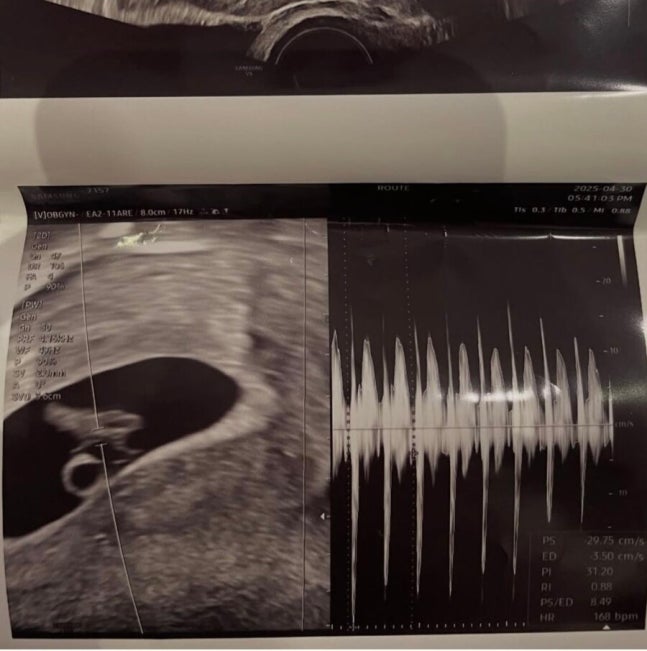

서민재는 2일 자신의 소셜미디어 계정에 "아빠 된 거 축하해"라며 임신을 나타내는 태아 초음파 사진을 게재했다.